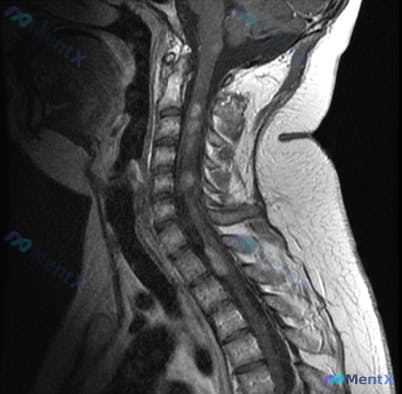

影像:颈椎MRI提示生理曲度变直,C4/5-C6/7椎间盘突出、椎管狭窄,C4-C7水平脊髓内见长T2高信号影。